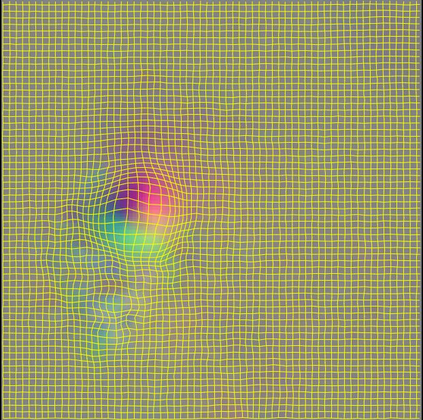

Image registration aims to establish spatial correspondence across pairs, or groups of images, and is a cornerstone of medical image computing and computer-assisted-interventions. Currently, most deep learning-based registration methods assume that the desired deformation fields are globally smooth and continuous, which is not always valid for real-world scenarios, especially in medical image registration (e.g. cardiac imaging and abdominal imaging). Such a global constraint can lead to artefacts and increased errors at discontinuous tissue interfaces. To tackle this issue, we propose a weakly-supervised Deep Discontinuity-preserving Image Registration network (DDIR), to obtain better registration performance and realistic deformation fields. We demonstrate that our method achieves significant improvements in registration accuracy and predicts more realistic deformations, in registration experiments on cardiac magnetic resonance (MR) images from UK Biobank Imaging Study (UKBB), than state-of-the-art approaches.